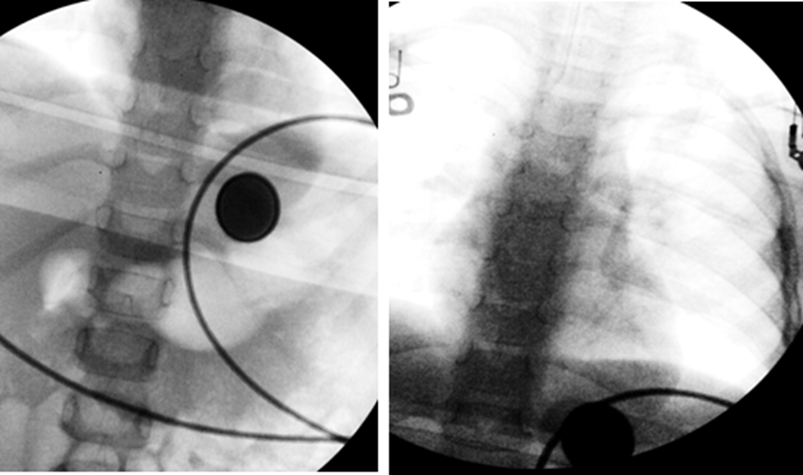

Intraoperative fluoroscopic images are shown below.

The foreign body was successfully removed from the distal esophagus via endoscopy.

• Intraoperative fluoroscopy: The previously observed metallic foreign body was visualized below the diaphragm.